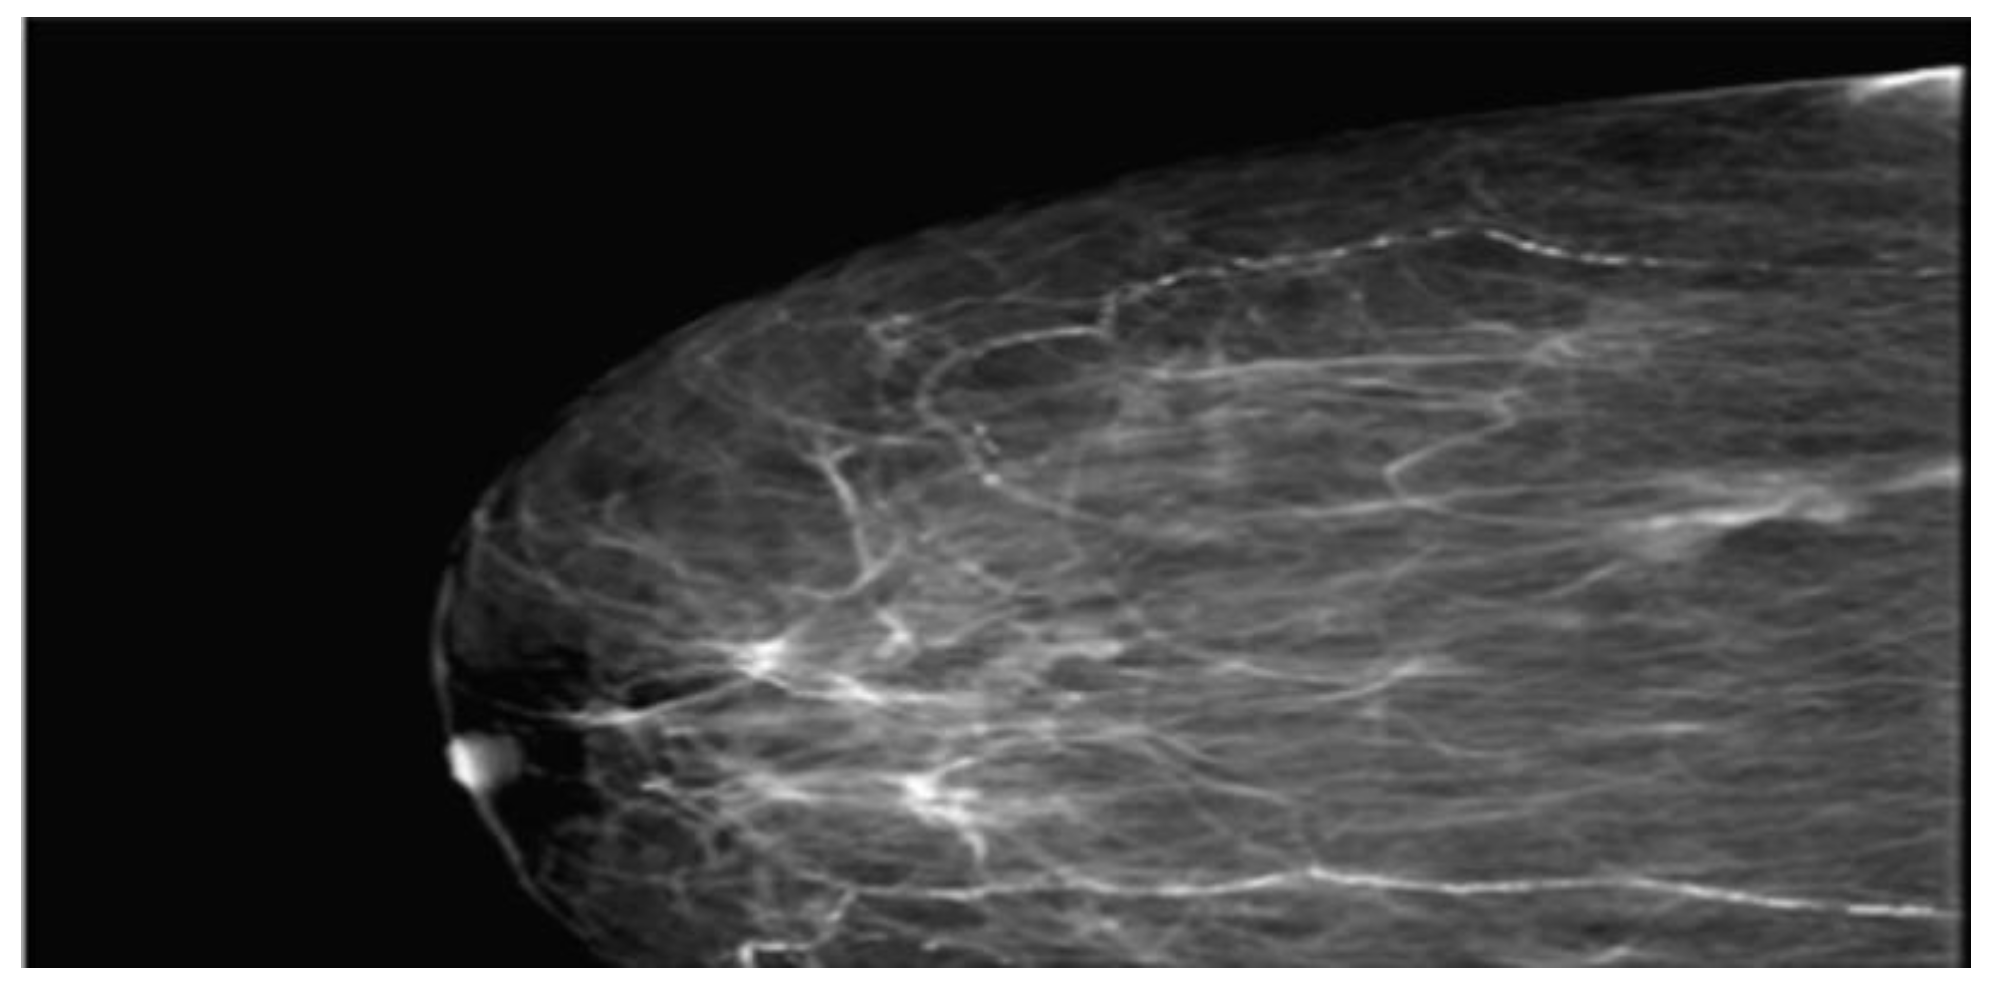

To establish a definitive diagnosis, a local anesthesia-guided core needle biopsy of the right breast was performed, obtaining 4 tissue fragments with a cumulative size of 25x1 mm. The microscopic histological structure suggested a Grade II SBR mucinous carcinoma (Figure 3).

Figure 3. Microphotography of the histopathological smear of the breast puncture biopsy shows abundant extracellular mucin and the cancer cells are scattered in the mucus basins.

The mucinous carcinoma component is composed of nests and cribriform-like structures floating in mucin lakes; tumor cells are polygonal, of medium size, with faint and focal cell boundaries, eosinophilic or pale cytoplasm, intracytoplasmic clear vacuoles, and small euchromatic nuclei, with some exhibiting a signet ring cell appearance (HE10X).